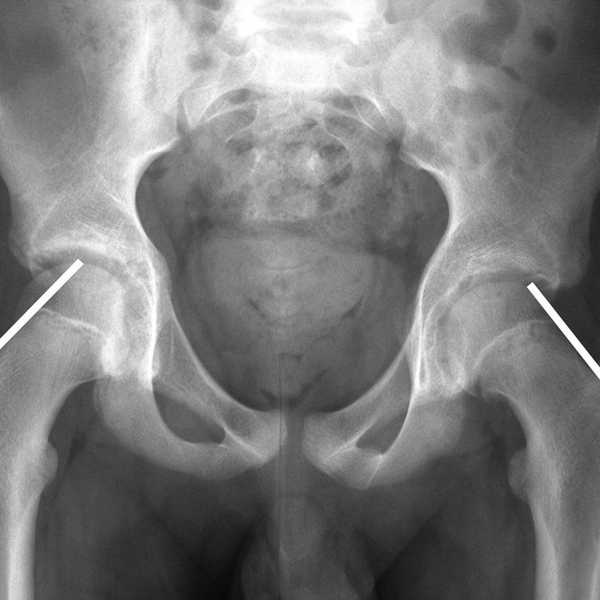

I was just standing there, in the middle of the floor -- literally just doing an arm movement. It was during a stupid, simple Mary Poppins dance. My ankle buckled and within a matter of a few seconds, my entire body collapsed over my foot. I tried to get up, but the agonizing pain prevented me from using my legs. My dance teacher panicked and called my parents who took me right to the emergency room. After spending the night there and basically high on pain meds, they concluded I had snapped my fourth and fifth metatarsals in half. They told me I wouldn’t be able to walk without a huge medical boot for six weeks.

For my follow-up x-ray a few weeks later, I was pretty nervous. I went to the children’s hospital and had to lay down in a dark room for a while. The ceiling was painted with tiles that some of the little patients drew, all positive, jubilant, and calming images. The one I was staring at was painted by a little girl that read the word ‘HOPE’ in big pink letters. The O was a smiley face. I started at it the entire time, hoping for the best. Hope is my favorite word and that tile really made me feel better throughout this entire journey. To just have some hope!